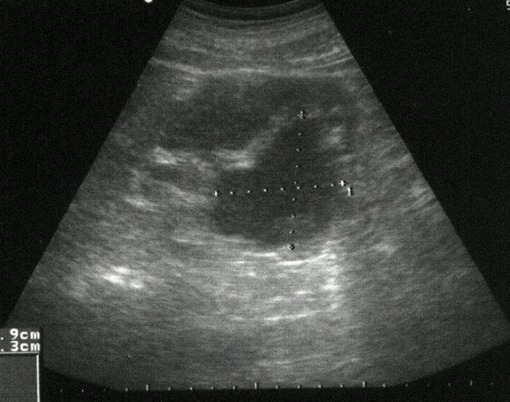

/ Obr. č. 2: Ultrasonografické vyšetření břicha /

Ultrasonografické vyšetření břicha: Játra nezvětšená, vyšší

echogenity, bez určitých ložiskových změn, žlučník bez patologického obsahu, žlučové cesty nerozšířené, pankreas a paraaortální oblast nepřehledné, slezina nezvětšená, normechogenní. Ledviny normálně uložené, do oblasti kalichopánvičkového systému pravé ledviny se promítá objemné nepravidelně konturované hypo až anechogenní ložisko rozměrů 59x63mm, levá ledvina bez ložiskových změn, bez městnání. Močový měchýř malé náplně, v malé pánvi bez nálezu volné tekutiny.

Závěr: V.s. mírná steatoza jater, objemné ložisko v oblasti kalichopánvičkového systému pravé ledviny - parapelvická cysta.